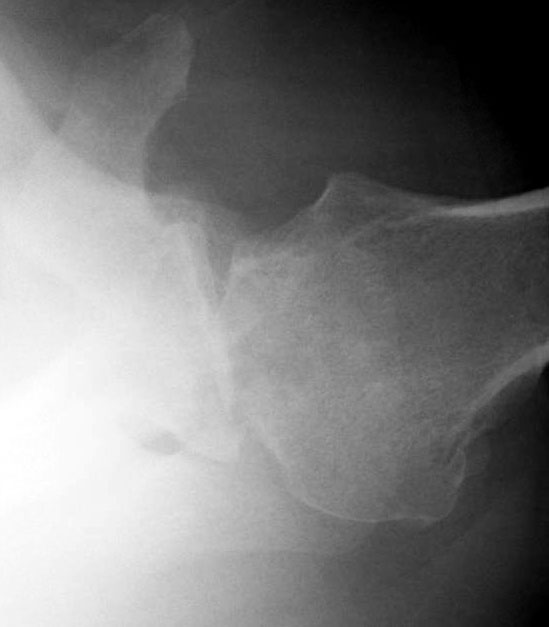

Osteoarthritis of the shoulder, Xray Stock Image C037/2762 Shoulder X Ray Views For Arthritis The projection demonstrates the shoulder in its natural. the shoulder ap view is a standard projection that makes up the two view shoulder series. the diagnosis of shoulder osteoarthritis involves a specific set of symptoms, physical examination findings, and changes to the bone, which are visible on. They can help distinguish among. shoulder radiographs are often the. Shoulder X Ray Views For Arthritis.